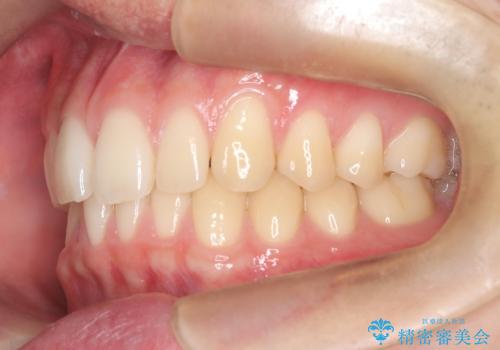

【ワイヤー矯正】すきっ歯を治したい

- 主訴:上の前歯のすきっ歯を治したい。

今回のような空隙歯列に対したは、マウスピース矯正・ワイヤー矯正どちらの方法でも矯正治療可能と説明し、ワイヤー矯正を希望されました。

上顎中切歯間の隙間の他にもフロスが抵抗なく入るスペースが上顎は数か所ありました。スペースを閉じ下顎の歯列弓との調和をとるためIPRを行いました。

下顎の舌側傾斜気味の前歯も唇側へ歯軸傾斜させています。

矯正期間:1年2か月